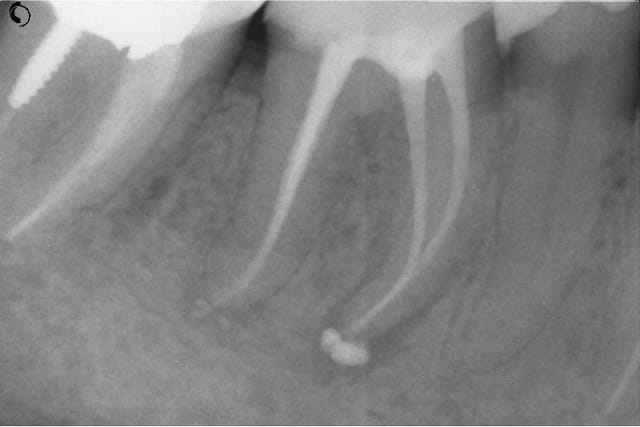

NB: ne pas chipoter svp sur l'appellation "kyste"

Kyste1 xpgssa - Eugenol

Kyste2 sef5wb - Eugenol

Repriseinit tk8kzi - Eugenol

Reprise4cx uandde - Eugenol